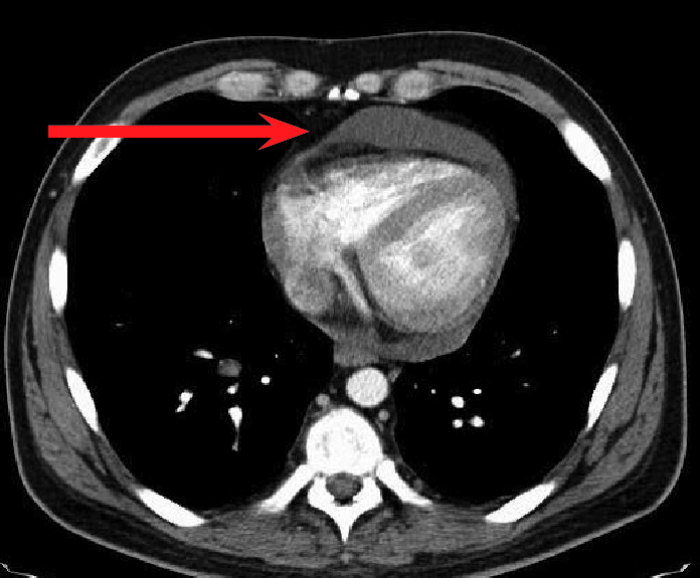

經(jīng)檢查,徐大爺被確診為結(jié)核性心包炎。

“該病起病隱匿,常有心外原發(fā)性結(jié)核病灶或同時有其他漿膜腔結(jié)核性積液存在,易出現(xiàn)長期低熱、盜汗、疲乏無力等癥狀,多無胸痛,易轉(zhuǎn)為慢性,最后形成縮窄性心包炎?!备腥究莆塘亮玲t(yī)生介紹,結(jié)核性心包炎為重癥結(jié)核病之一,對患者生命、生活質(zhì)量均可造成嚴(yán)重影響。

確診結(jié)核性心包炎后需要規(guī)律治療,防止病程進展到縮窄階段,降低死亡率。由于徐大爺基礎(chǔ)疾病較多,感染科團隊為其量身定制了個體化抗結(jié)核治療方案。